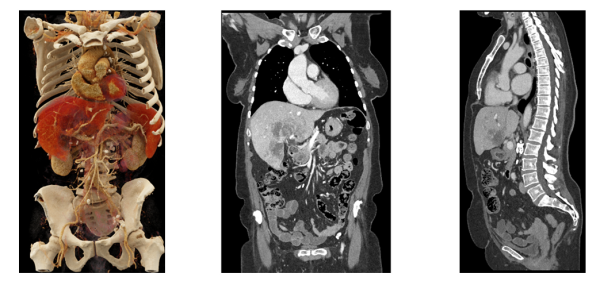

NAEOTOM Alphaの「フォトンカウンティング検出器を搭載した最新のデュアルソースCT(2つのX線管と検出器を搭載したCT)」といった大きな特徴を活かしたスペクトラルイメージングにより、1秒未満といった短い時間での70cmを超える広範囲の撮影、心臓など動きのある臓器においても高精細な画像の取得が可能となる。息止めが難しい場合や小児など様々な状況にある患者の負担軽減を実現しながら、様々な疾患において早期発見や正確な診断への貢献が期待されている。

名古屋市立大学大学院医学研究科 放射線医学分野 樋渡昭雄教授は、「NAEOTOM Alpha が持つ高い空間分解能は、血管系の描出、動脈瘤の詳細な解析、動脈解離の評価といったものに非常に役に立つと考えております。CTによる血管撮影で詳細な評価を行う事が出来れば、カテーテルを用いた診断の血管撮影が省略できる可能性があるのではないかと期待しております。また、仮想単色X線、ヨードマップ等のスペクトラルイメージングを活用し、理想的には抗癌剤の分布等も分かれば、臨床的に非常に有用ではないかと思います。」と述べている。

本製品は、Siemens Healthineersがアクロラドとともに開発した「フォトンカウンティング検出器」を搭載している。主に被ばくを低減しつつ高分解能な画像を臨床利用できるという点で、従来のCT装置から大きなイノベーションを果たした。

フォトンカウンティング検出器は、従来の検出器のようにX線光子を可視光に変換するのではなく、各X線光子とそのエネルギーレベルを直接検出するため、より少ない放射線量で高解像かつ有用なデータを提供することができる。また、被ばくを抑えることができるため、患者や検査を受ける人の負担を減らしつつ正確で包括的な検査が可能となる。その応用範囲は、腫瘍や心臓の診断から肺のフォローアップ検査まで、幅広く多岐にわたる。